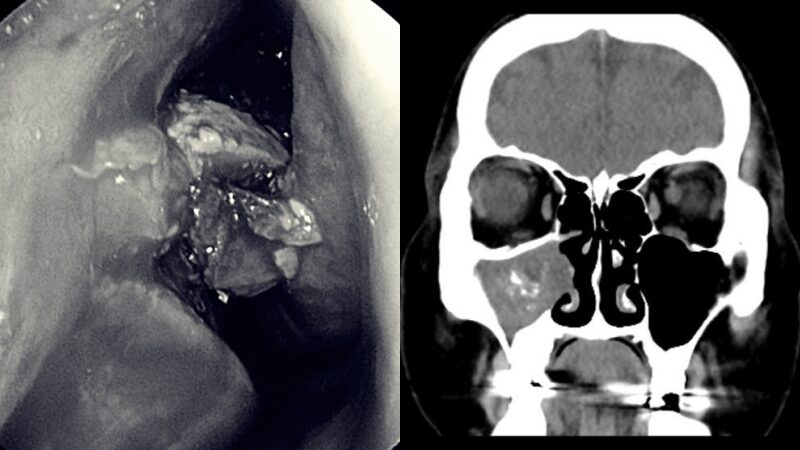

เมื่อไม่นานมานี้ ดร. เฉิน ซื่อซีเผยแพร่องความรู้ทางการแพทย์ผ่าน 耳鼻喉科 陳世璽醫師 พร้อมโพสต์ภาพก้อนแปลกประหลาดที่มาจากร่างกายคนไข้หลังการผ่าตัด

หลังจากฟังคำอธิบายของผู้ป่วยแล้ว แพทย์รู้สึกว่า นี้ไม่ใช่อาการของไซนัสอักเสบเฉียบพลันธรรมดา แพทย์จึงนัดให้ผู้ป่วยทำซีทีสแกนไซนัส จากนั้นพบว่าไซนัสขวาของเธอถูกก้อนเชื้อราขนาดใหญ่อุดตันจึงวินิจฉัยว่าผู้ป่วยเป็น "ไซนัสอักเสบจากเชื้อรา" และแนะนำให้เธอรับการรักษาด้วยการผ่าตัดและดูดเสมหะที่มีเชื้อราออกจากโพรงจมูกทั้งหมดอย่างระมัดระวัง

จากการตรวจเอกซเรย์คอมพิวเตอร์ หรือเรียกว่าซีทีสแกนของไซนัสพบว่า ไซนัสขากรรไกรบนขวาเต็มไปด้วยจุดแคลเซียมที่สว่าง นพ. เฉิน ซื่อซี กล่าวว่า นี่เป็นอาการทั่วไปของการติดเชื้อราในไซนัสที่ก่อตัวเป็นก้อนเชื้อรา ซึ่งเป็นไซนัสอักเสบแบบไม่รุกราน

โดยทั่วไปต้องใช้การผ่าตัดระบายของเหลวออก ในที่สุดก็ทำการผ่าตัดไซนัสด้วยกล้องเอนโดสโคปแบบใช้งานได้สามารถขยายช่องเปิดไซนัสใต้กล้องเอนโดสโคป และใช้เครื่องมือล้างเพื่อขจัดเชื้อราที่สะสมอยู่ในไซนัสออกให้หมด